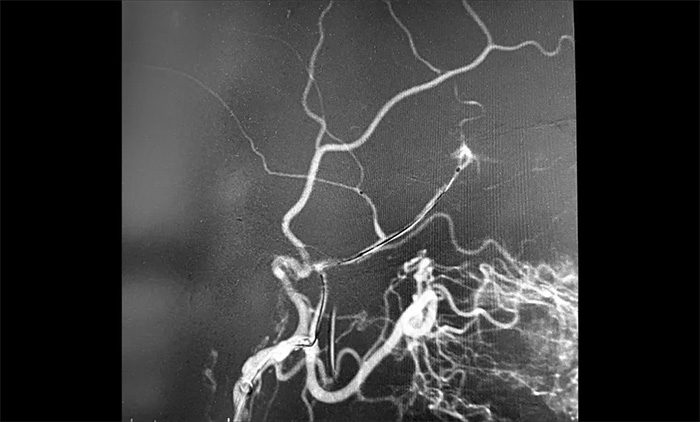

12月29日,顺利进行手术。术中,王贵平博士在介入团队协助下克服血管迂曲的困难,导管精准到达左脑膜中动脉前支、左脑膜中动脉后支,之后缓慢注入液体栓塞剂,栓塞剂逐渐向脑膜中动脉主干反流,复查造影,左脑膜中动脉无明显前向血流,手术成功。术后,患者无新发神经功能缺损。言语不清,肢体活动不利,头晕等症状逐步好转。

▲ 术中